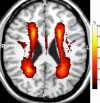

Objectives: To compare magnetic resonance imaging data with functional assessments of mobility, urinary control, and cognition to determine common or distinctive features in the distribution of brain white matter hyperintensities (WMHs) associated with functional decline and impairment.

Measurements: WMHs were identified using a semi-automated segmentation method, and regional burdens were assessed using a white matter parcellation atlas. Quantitative measures of mobility, urinary incontinence (UI) severity, and executive function and processing speed were obtained.

Results: WMHs occur predictably in predominantly periventricular areas. There were powerful correlations between total (tWMH) and regional (rWMH) WMH, with correlation coefficients of 0.5 to 0.9 for eight of 10 structures analyzed. tWMH predicted functional measures of UI, mobility, executive function, and processing speed nearly as well as the best regional measures. The total volume of WMHs independently explains 5% to 11% of the variability for mobility, UI severity, executive function, and processing speed and is a sensitive (0.7-0.8) predictor of functional decline. The odds of decline in each of the three functional domains was 1.5 to 2.4 times greater with each 1% increase in tWMH.